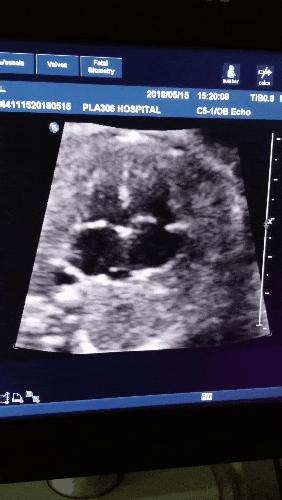

二、卵黄囊(Yolk Sac)

b超的3组数字代表什么,b超图片上的数字

卵黄囊是附着在胚胎上的膜囊,是妊娠囊内超声能看到的第一个解剖结构。